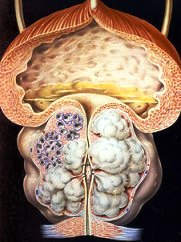

Саркома простаты

По гистологическому строению чаще всего встречаются фибросаркома, лимфосаркома, миосаркома, реже — миксосаркома, хондросаркома и рабдомиосаркома.

Более поздние признаки заболевания связаны как с прорастанием опухоли в окружающие ткани, так и с ее метастазированием, и проявляются выраженной кахексией, жестокими болями внизу живота, за лобком, в промежности. При пальцевом исследовании через прямую кишку определяется деревянистой плотности, часто бугристая и лишь иногда гладкая, малоболезненная предстательная железа.